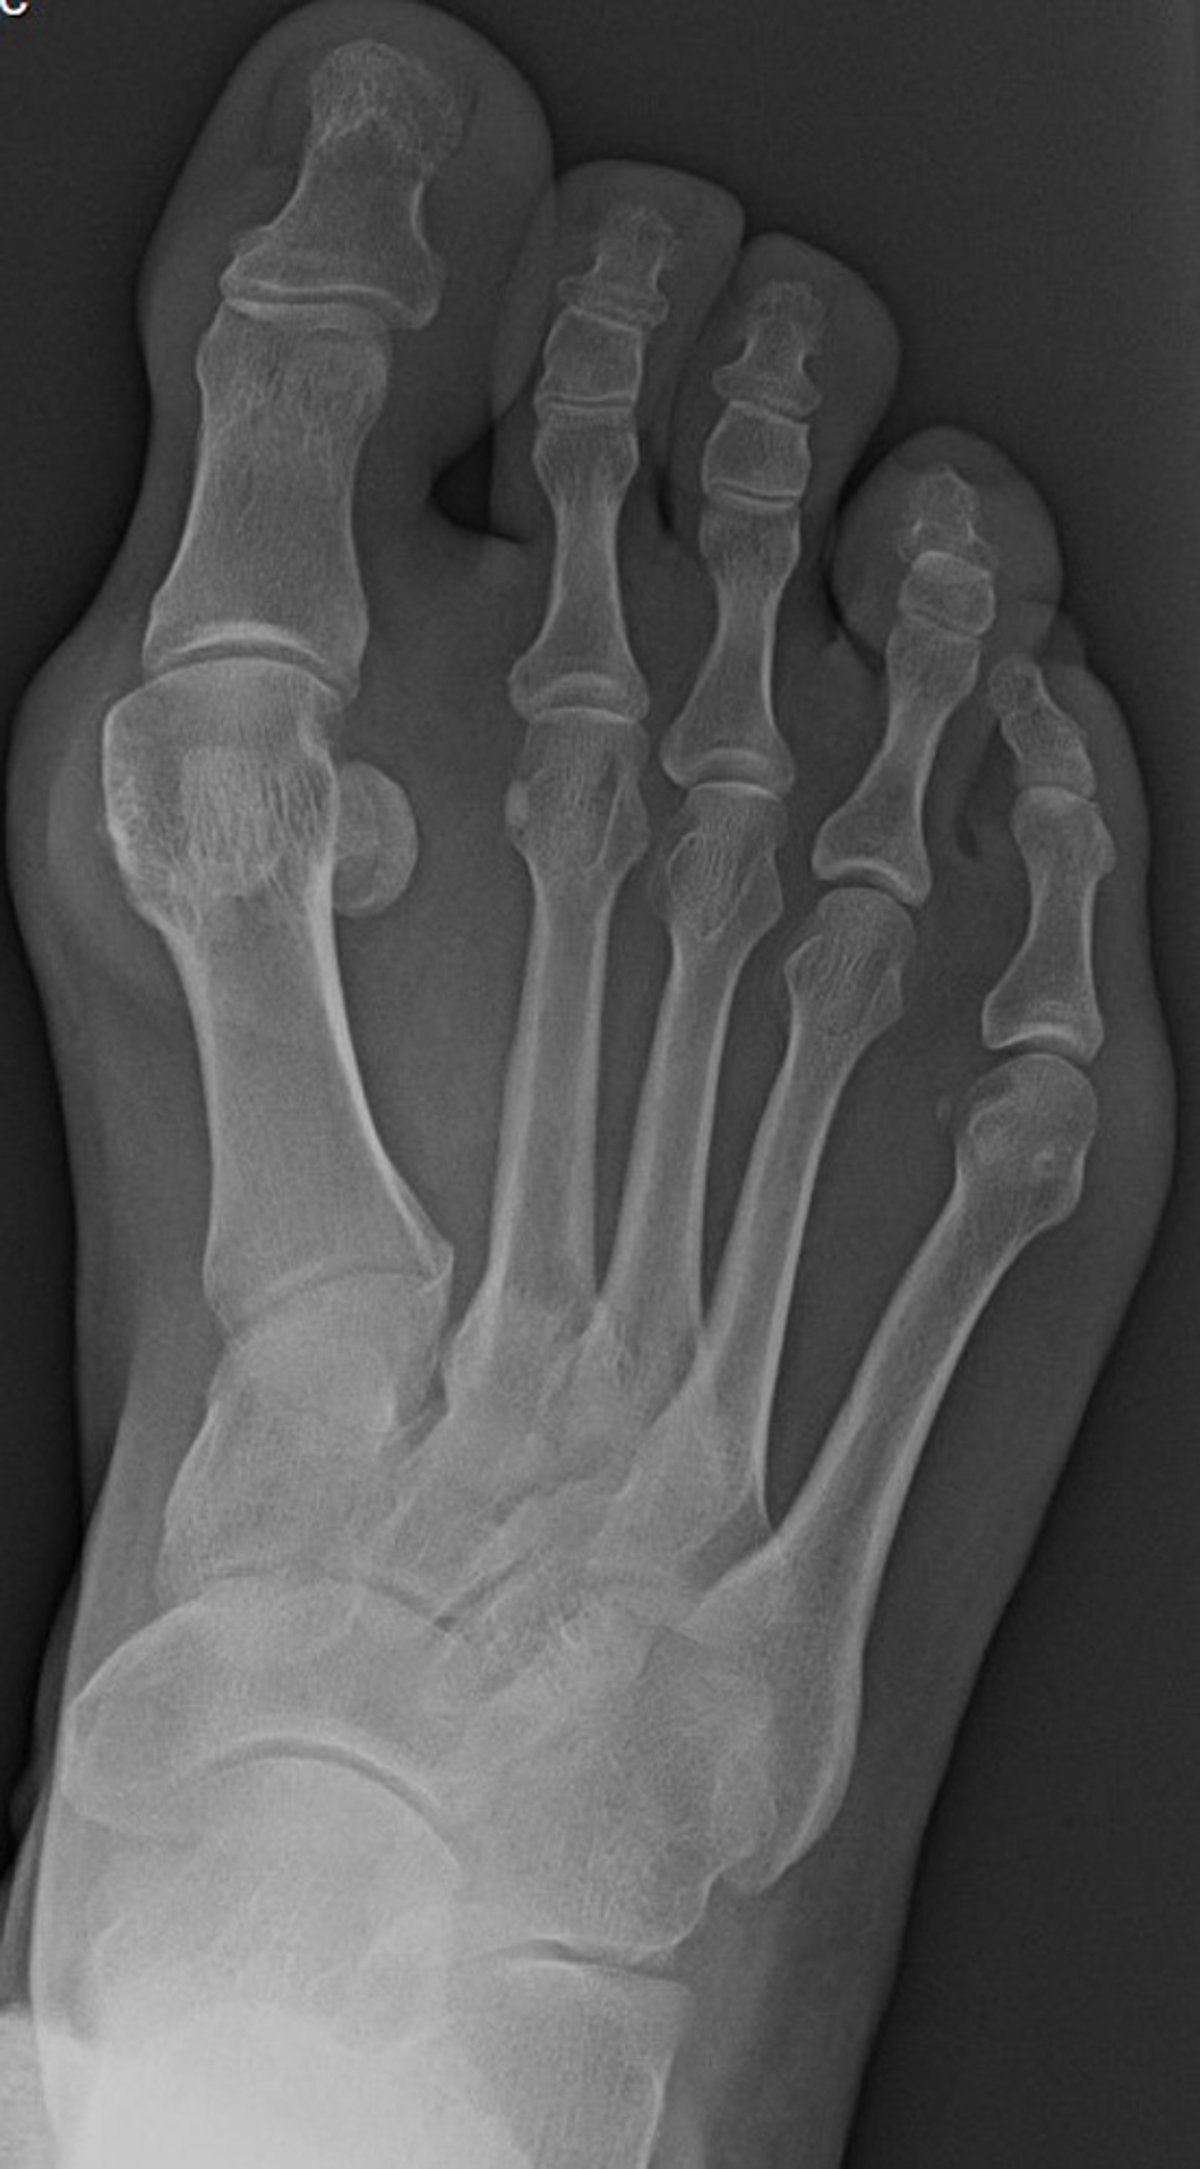

Anteroposterior (AP) Radiograph of Foot with Bunion

This anteroposterior view of the foot shows radiographic findings consistent with hallux valgus, with medial deviation of the first metatarsal. There is also lateral subluxation of the base of the first proximal phalanx with respect to the head of the first metatarsal.

Image courtesy of James C. Connors, DPM.